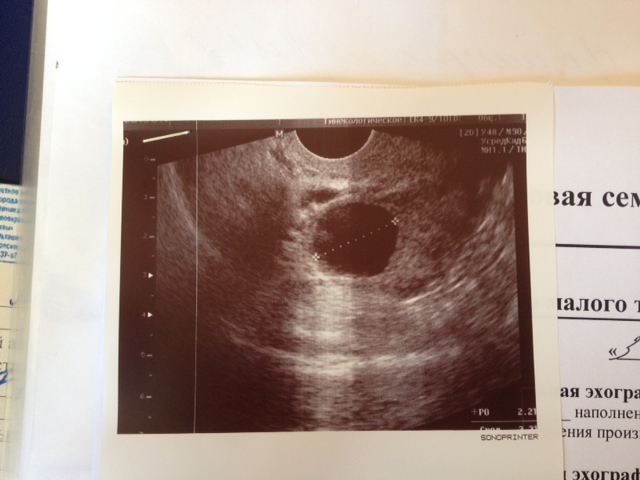

Овуляция( тесты на овуляцию)Прочитала, что девочки мне ответили за выходные на последний пост, всем ответила)и решила сделать тест на О, тк все в 90%говорили, что скорее всего О, но я ведь нет-верю только этой врачихе из инвитро, которая увидела у меня желтое тело на 15 деньи по определению ждать о уже не было смысла!!!И открещивалась от О до последнего. И вот замочила тест и через 5 миниут иду его смотреть, а там....наижирнейшая полоска, она даже изначально была раза в ярче осовной!!!Я в шоке и ступоре...блин, но вот не зря же тем-ра падала и вчера-сегодня поясница и яичник болит!!!Все вроде хорошо и я рада, что она вот вот будет, но меня жутко бесят вот такие во спецы кот. и мне, и многим еще карты все путают, а из-за этого месяцы идут впустую....Как можно перепутать ЖТ с доминантным фолликулом???Как???так вот оно 29/05 было 12мм, я в уме прикинула, что если оно растет по 2 мм в день, то должно быть 20-22мм, побежала на узи в свой центр, там хорошая узиста!Так вот она сказала, что это действительно ДФ и никакого тут ЖТ нет(((я в шоке....ну, а если бы вы меня не навели на эту мысль, если бы я не сдела тест,то все еще месяц в пролете.....рррр